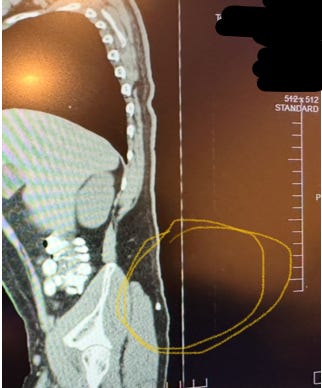

Mon patient a subi plusieurs examens d'imagerie révélant la présence de micropuces implantées. Ces emplacements correspondaient aux zones de torture les plus sévères. Ci-dessous, vous pouvez voir une micropuce entourée :

Il y en a un autre à la base du sacrum :